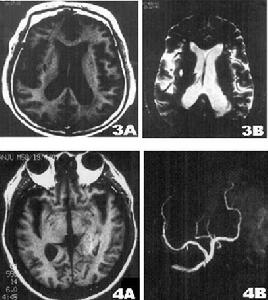

兩側半卵圓中心側腦室旁深部腦白質呈不甚對稱的長T1WI長T2WI信號,無占位效應,在T1WI圖像上呈低信號,T2圖像上呈高信號,全部病人腦室擴大,腦溝增寬,腦池擴大,表現為腦萎縮特徵。78例(89.6%)為多發性腦梗塞,9例(10.3%)為單發性腦梗塞,其中6例(6.9%)伴出血灶,男2例,女4例,其13例(14.9%),CT未發現腦梗塞,由MRI明確診斷。主要是對腦內脫髓鞘改變的範圍和腦萎縮的程度,特別是塞灶的大小,部位,腦缺氧早期診斷是否合併出血,這樣,對患者確定治療方案及預後有著深遠的意義。

影像學表現:CT表現為斑片狀及斑點狀低密度影,MRI表現為點狀及片狀長T1WI長T2WI信號,由腦深部灰質團塊萎縮,胼胝體繼發變薄,致使腦室擴大,又由於瀰漫性髓鞘脫失而有不同程度的腦萎縮,顯示腦溝增寬,腦池擴大(如圖1~4)。有高血壓及動脈硬化的病理基礎也可發生腦出血是腔隙性梗塞的直接原因。

賓斯旺格病診斷及鑑別診斷:CT,MRI的問世,為本病的生前診斷提供了影像學依據,CT表現為雙側腦室旁白質區與半卵圓中心顯示散在性或融合性低密度區,對稱或大致對稱,基底節,內囊與丘腦區可見多發性腔隙性梗塞,重者伴腦室擴大,其室管膜面多參差不齊,呈碎布狀。MRI表現:在腦室周圍白質與半卵圓中心顯示散在或融合性病變區,T1WI呈黑色,T2WI呈白色。重度與中度顯示腦室擴大,腔隙性梗塞顯影清晰,病灶數目比CT發現的多。SAE應與多發硬化,嚴重腦積水所致的室管膜水腫,CO中毒腦水腫期,腦囊蟲病腦炎型,ALZHEIMER氏病,PICK病,及其他特異性腦白質病,這些腦白質病變根據CT,MRI的表現特點,結合臨床表現60歲以上潛隱起病,逐漸加重,若具備卒中發作,高血壓,慢性進行性痴呆三大臨床特徵,綜合分析,即可做出診斷,也可隨訪複查。

SAE經CT,MRI檢查可明確診斷,CT檢查在發病24h內往往陰性,顯病灶數目少,腦幹,後顱窩病變及視神經通路(視放射)的損害未能顯示而遺漏,但CT價格低,易普及,對腦組織缺氧24h後,CT值即降低,並對缺氧引起的顱內出血及出血量有客觀指標。而MRI在診斷SAE方面比CT更優越,表現在:①MRI在腦細胞毒性水腫6h即可發現病變。②MRI發現病灶數目多。③MRI能夠清楚顯示腦幹,後顱窩病變及視神經通路,顳角部位病變。④MRI可行矢狀,冠狀掃描,多方位觀察。⑤MRI可顯示VIRCHOWROBIN間隙。